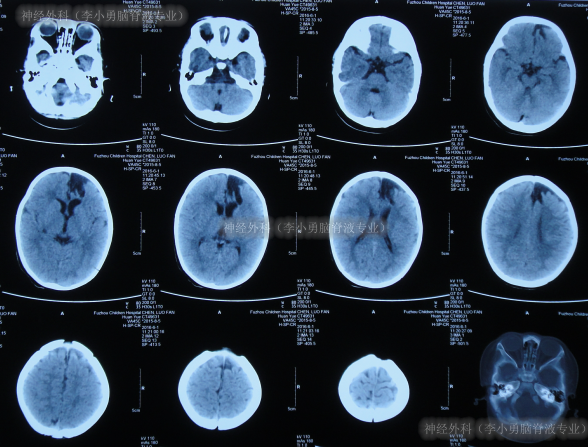

入院时头颅CT示癫痫术后,左侧额顶骨术后改变,左侧侧脑室引流术后状态,幕上脑室系统扩,多处硬膜下积液、部分见积气(图-16)。

图-16:2017年7月20日头颅CT